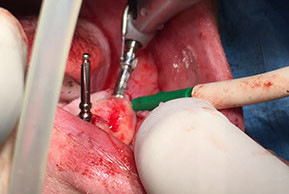

IMPLANTOLOGIA

L’implantologia dentale è quella disciplina che consente il recupero della masticazione e e dei denti mancanti attraverso l’utilizzo di radici artificiali in titanio dette: impianti endossei

Il titanio è il materiale piu biocompatibile attualmente in uso.

L’intervento per il posizionamento dell’impianto o degli impianti è generalmente di breve durata e non comporta nessun tipo di dolore.